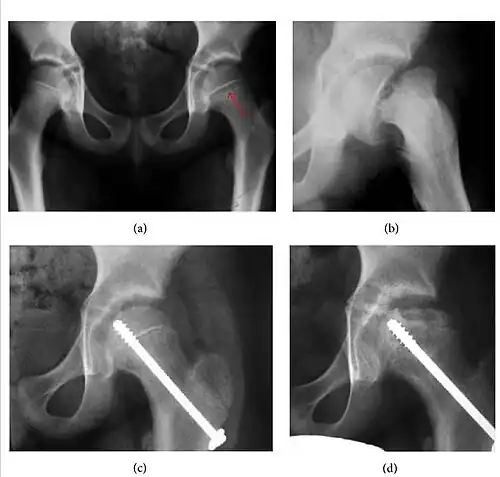

Slipped capital femoral epiphyses (SCFE) usually affect 11- to 14-year-old adolescents (Figure 4). Radiographs may show widening and irregularity of the physis and posterior inferior displacement of the capital femoral epiphysis. On the AP view Klein’s line, tangent to the lateral aspect of the femoral neck, does not intersect the femoral head indicating that it is displaced. SCFE may compromise the blood supply to the femoral head and cause avascular necrosis, mainly when there is instability between the fragments.[1]

-

Figure 4: (a) X-ray of a 10-year-old child with left hip pain. It was considered normal at emergency despite the widening of the left physis (arrow). Two weeks later epiphysiolysis was evident (b). Despite appropriate surgical reduction (c) osteonecrosis developed and femoral head collapsed 1 month later (d).[1]